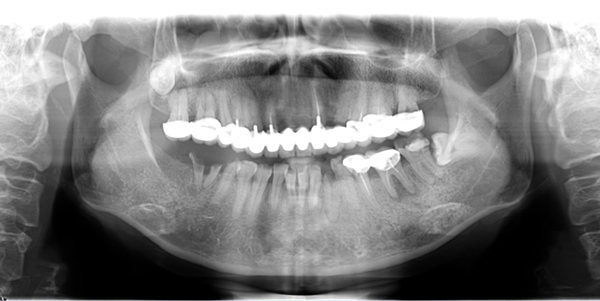

郄女士做口腔ct检查

郄女士口腔ct全景片